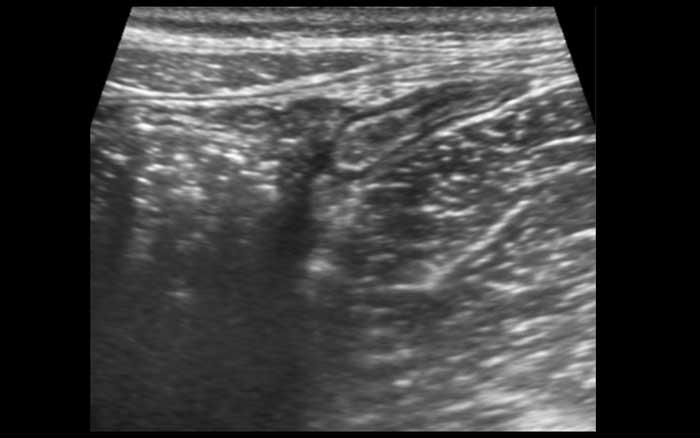

Ruột non bình thường có thể dễ dàng quan sát bằng siêu âm và được nhận biết qua nhu động ruột liên tục và rõ ràng, ngay cả khi lòng ruột trống rỗng.

Lưu ý nhiều vùng giảm âm nhỏ hình tròn với đường viền tăng âm trong lớp dưới niêm mạc sáng.

These represent normal 0.4 – 0.5 mm vessels.

Cũng lưu ý đường tăng âm mỏng bên trong lớp cơ, đại diện cho mô liên kết ngăn cách lớp cơ dọc và lớp cơ vòng, chứa đám rối Auerbach.

Normal small bowel in the longitudinal plane.